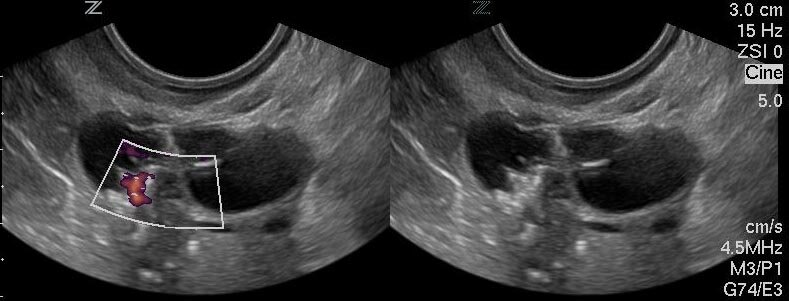

Очень часто формирование кисты не сопровождается какими-либо симптомами. Как правило, обнаруживают образование совершенно случайно при проведении планового ультразвукового исследования органов малого таза.

Кистой яичника называют образование, которое представляет собой полость, заполненную жидкостью и окруженную плотной капсулой. Опухоль имеет доброкачественный характер. Рост обусловлен увеличением объема жидкости.